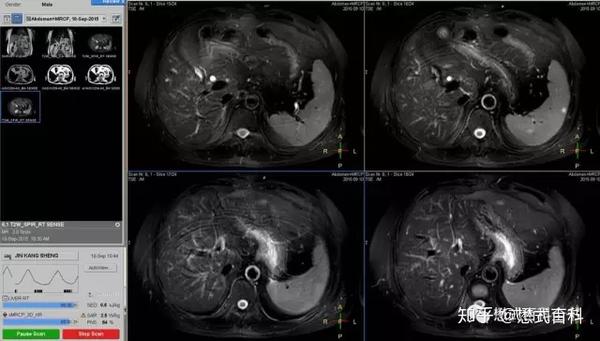

磁共振上腹部快速自动化增强扫描流程的初步研究 罕见病 疑难病 会诊平台 专家会诊 网上会诊 医学影像

MRI(magnetic resonance imaging)検査では撮像 時間が長く,上腹部の検査では,呼吸による動きによ ってモーションアーチファクト(mortion artifact:運 動アーチファクト)が発生し,読影診断に影響を与え てしまうおそれがある.呼吸のような周期的な動きに. 3T MRI が臨床に導入されてから、基本的な撮像技術の重要性がますます高まっている。本講演では、3T MRIにおける躯幹部領域のトピックスである、脂肪抑制、Volume化の流れ、非造影MRAの3点について、GE社MRIの最新アプリケーションと臨床的有用性を中心に紹介する。. く,造影剤が分布した周囲組織のプロトンの緩和を促進(主としてt1短縮効 果)させることにより,t1強調画像で造影効果を発揮する(信号が増強される)。 しかしながら,造影剤濃度が高くなると,t2,t2*短縮効果により信号は逆に 減衰する(図1)2)。.

长海医院经验分享 5分半钟完成高质量的腹部mri检查 磁共振爱好者 微信公众号文章阅读 Wemp